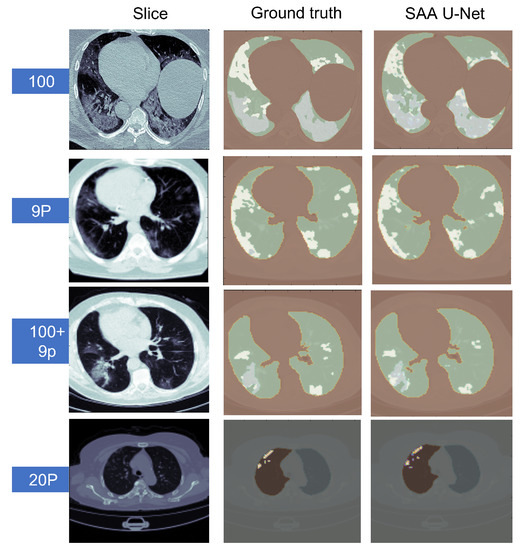

6.3. Multi-Class Classification